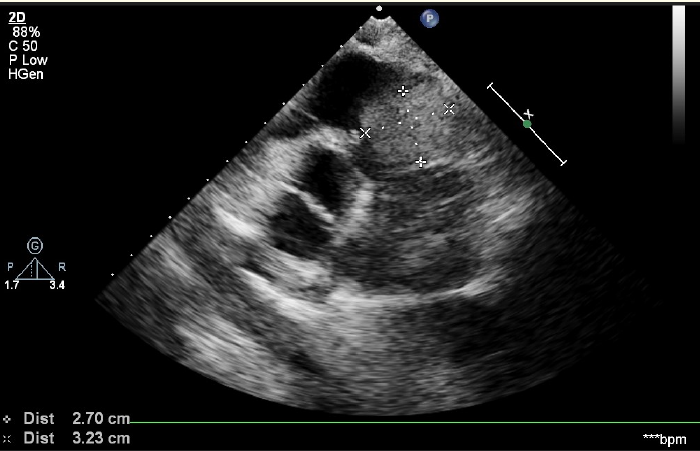

Right Ventricular Myxoma Obstructing RV Inflow and Causing Pulmonary Embolism: Management and Brief Review

Sukhvinder Singh, Mohammad Mubeen and Sanskriti Bhardwaj. 10(1): 37-41.